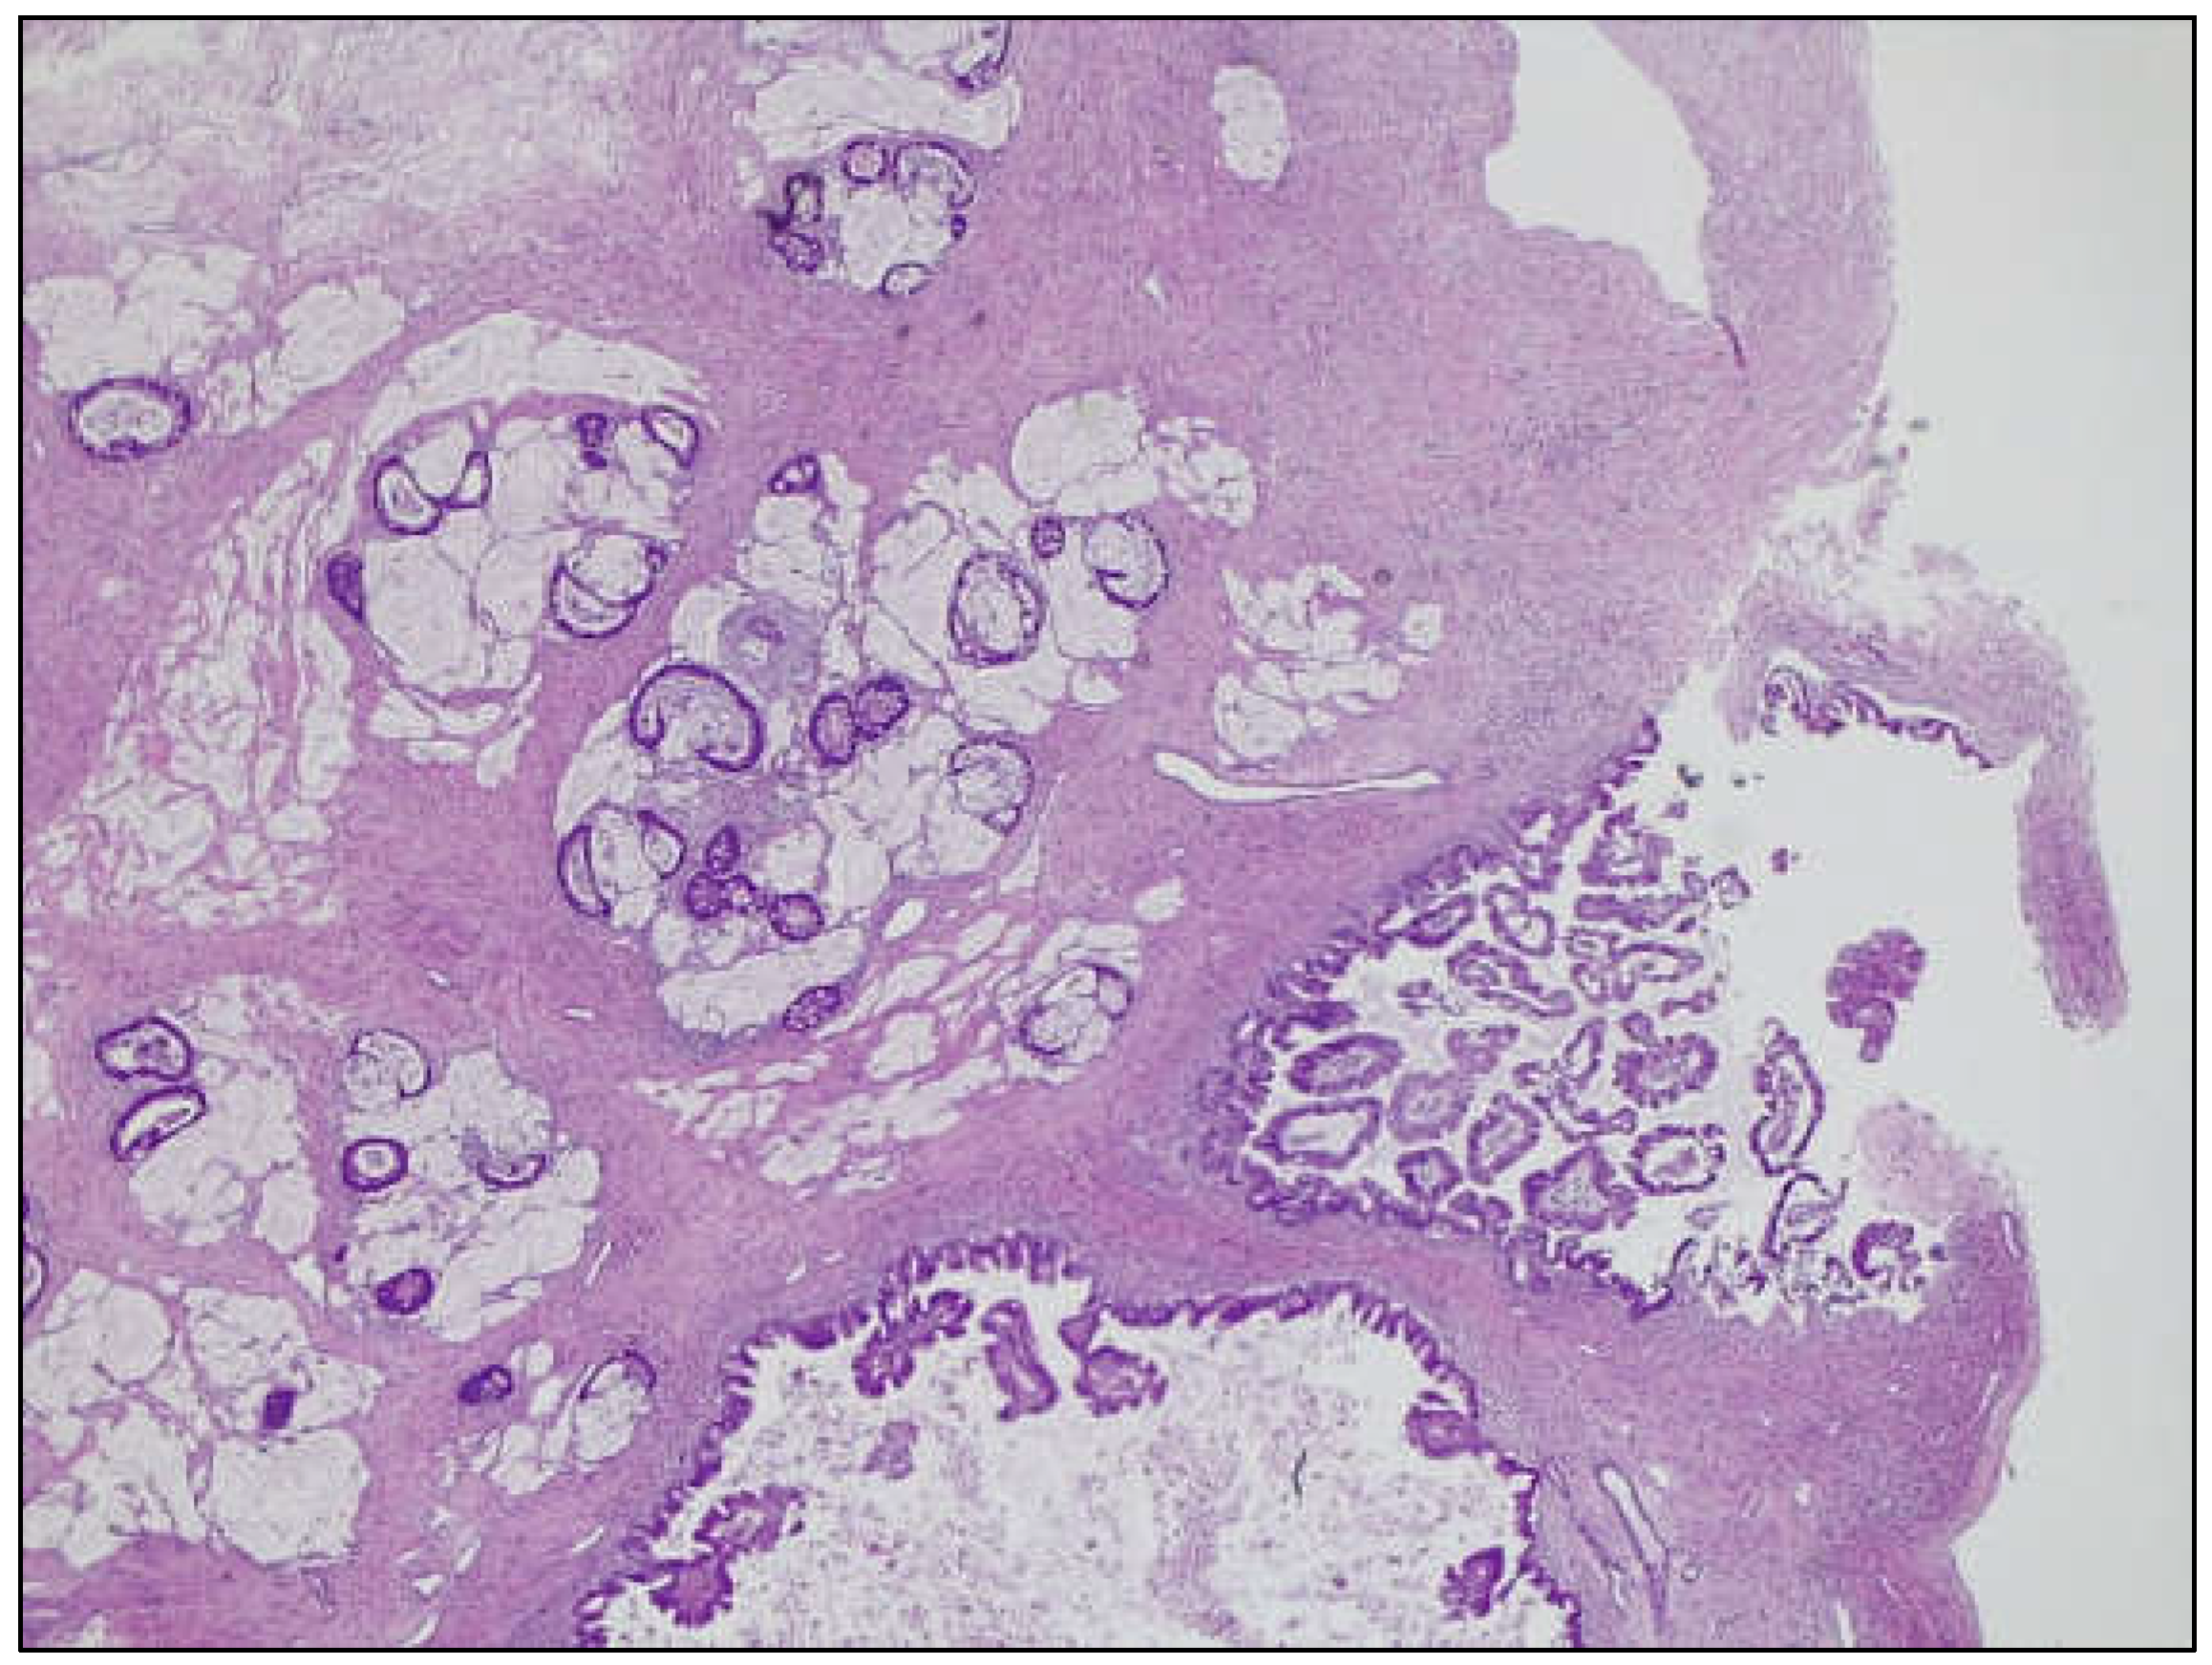

Mucinous Carcinoma, Mucinous Borderline Tumor and Pseudomyxoma Ovarii in a Cystic Teratoma: A Histological Conundrum

Giacometti, C.; Mirandola, M.; Aliberti, C.; Molinari, F.; Marcolini, L.; Mautone, D.; Martignoni, G. Mucinous Carcinoma, Mucinous Borderline Tumor and Pseudomyxoma Ovarii in a Cystic Teratoma: A Histological Conundrum. Diagnostics 2025, 15, 1957. https://doi.org/10.3390/diagnostics15151957